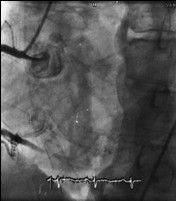

一例63岁男性因“气促”入院。既往有高血压、卒中和酒精滥用史。入院时心率120次/分,颈静脉充盈,第一、第二心音规则,胸骨左缘可闻及Ⅲ~Ⅳ级全收缩期杂音,吸气时增强。超声心动图提示弥漫性左室运动功能减退,室间隔远端节段性无运动。LVEF为30%。心导管检查未显示冠脉闭塞,而发现在RCA和右室之间存在一处2 mm长的瘘道(如图)。